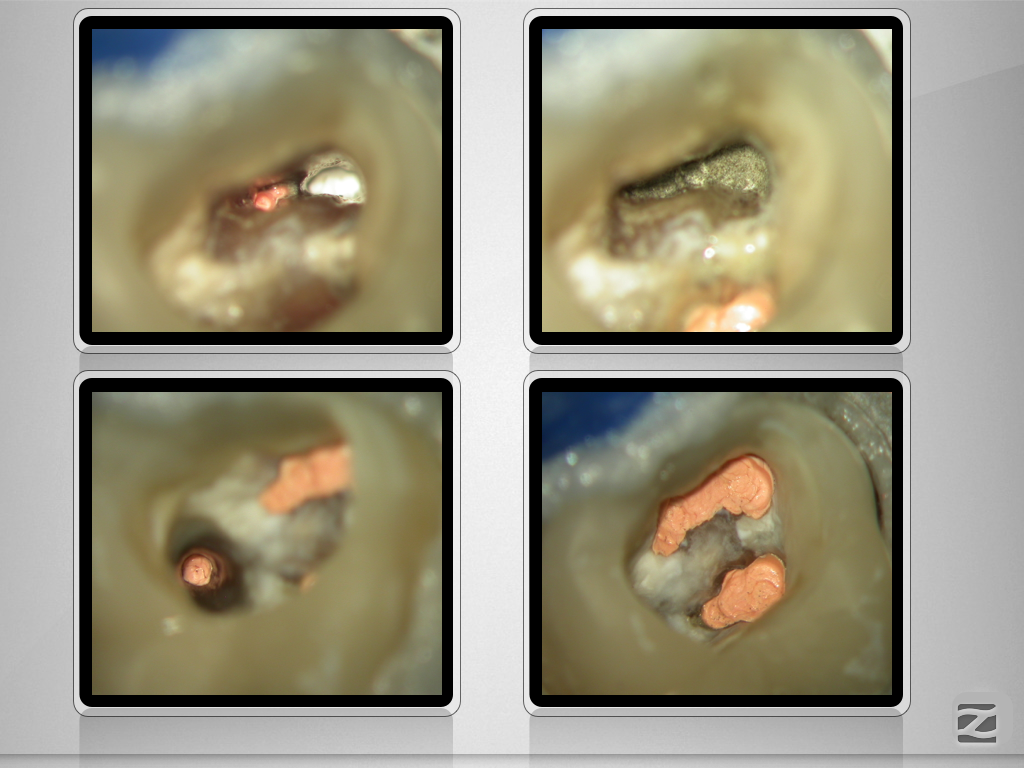

X-Bein/H-förmiger Isthmus/tiefer Split